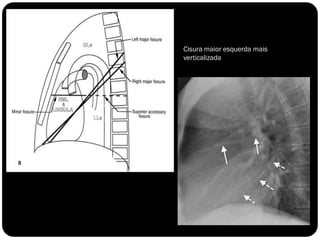

Pulmões – lobos - fissuras

 Direito: 3 lobos (fissura oblíqua = maior e a horizontal =

menor)

 Esquerdo : 2 lobos (fissura oblíqua)

 Fissuras interlobares: invaginações da pleura;

Cisura maior esquerda mais

verticalizada

Pleuras – derrame pleural intrafissural